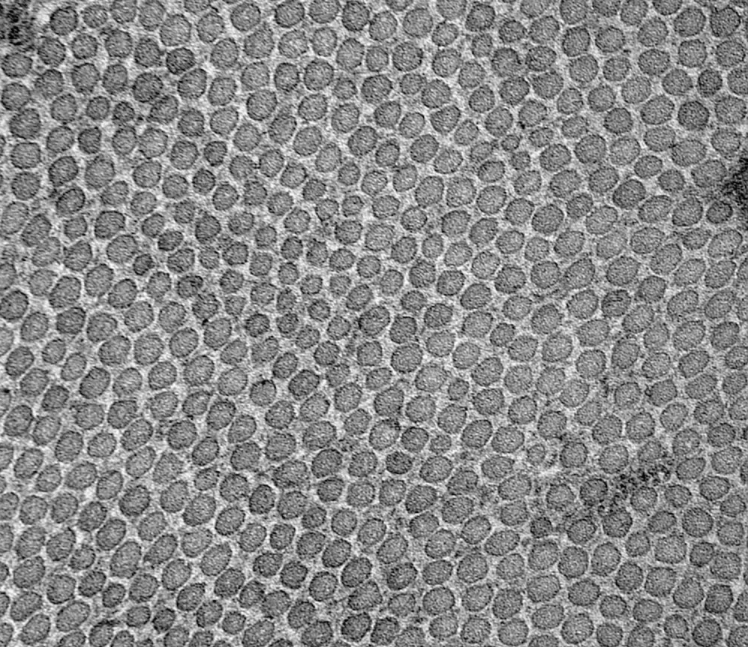

图3-1-3弹性纤维光镜图 图3-1-4弹性纤维